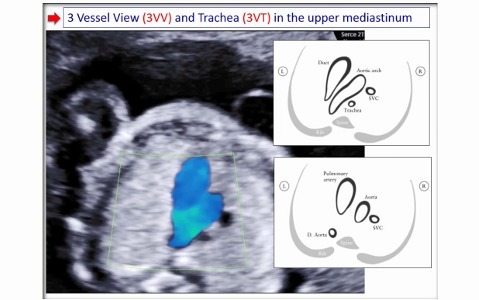

2nd European Congress of IAN Donald School